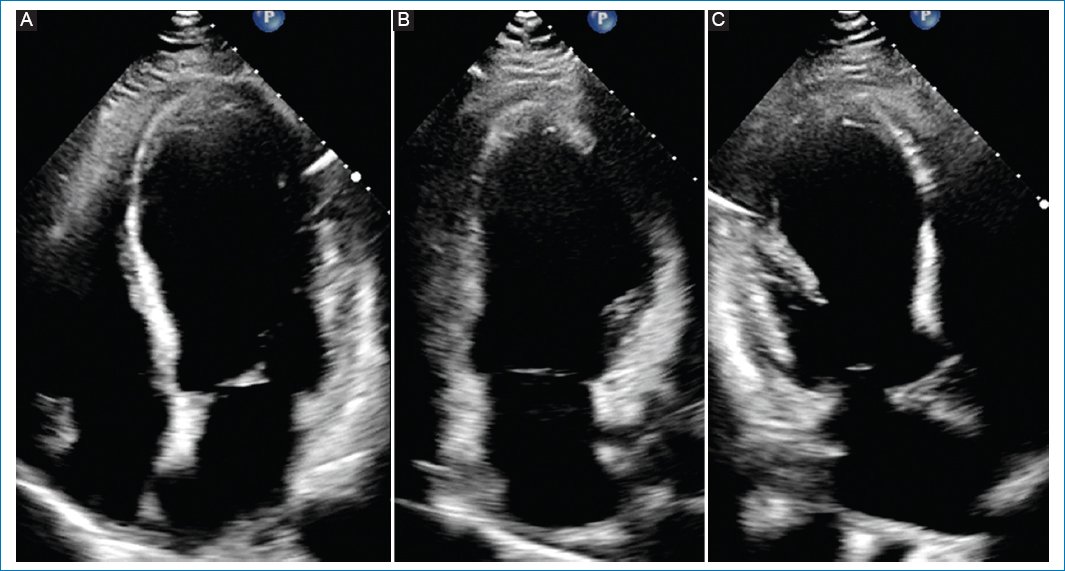

The electrocardiogram was relevant for persistent ST elevation on leads V2 and V3, T-wave inversion of leads DI, aVL, V2-V6, and Q-wave in leads DI, aVL, V1-V3, suggestive of an evolved anterior ST-elevation myocardial infarction (STEMI) (Fig. 1). The results of blood tests revealed high levels of troponin and brain-type natriuretic peptide (Table 1). The computed tomography (CT) scan of the head showed an ischemic infarct in the posterior cerebral artery territory (Fig. 2). The transthoracic echocardiogram (TTE) revealed dyskinesia of the apical septal, mid-inferoseptal, apical anterior, and mid-anterior walls; hypokinesia in the basal inferoseptal, apical lateral, mid-anterolateral, and basal anterior walls; and akinesia in the apical inferior, anteroseptal, and apical lateral walls of the left ventricle. The patient had a left ventricular ejection fraction (LVEF) of 36%, no right ventricular systolic dysfunction, and no valvulopathies (Fig. 3).

Figure 3. Transthoracic echocardiogram showing wall-motion abnormalities. A: apical four-chamber view: apical septal with mid inferoseptal dyskinesia, basal inferoseptal hypokinesia, and apical lateral with mid anterolateral hypokinesia. B: apical two-chamber view: apical inferior akinesia, apical anterior with mid anterior dyskinesia, and basal anterior hypokinesia. C: apical three-chamber view: anteroseptal and apical lateral akinesia.

AMI is most associated with ST-elevation (56-78.6%) with occlusion of the LAD (68.8%), followed by right coronary vessels (31.3%). The main findings of the echocardiogram are an LVEF < 50% (38-83.3%) and regional wall motion abnormalities (50-74.1%)1,6. In this case, the patient had a history of active smoking and presented to the emergency department with anterior-wall STEMI and mild AIS affecting the posterior cerebral circulation 24 h after the onset of symptoms. Echocardiography showed low LVEF with wall motion abnormalities according to the LAD territory.